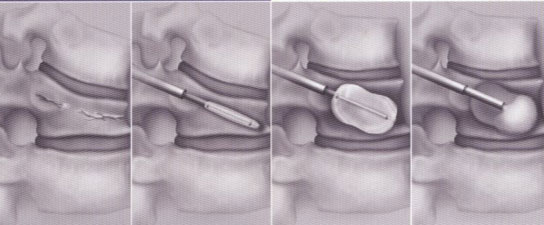

Bei der Kyphoplastie handelt es sich um eine Variante der Vertebroplastie. Genau wie bei der konventionellen Vertebroplastie werden unter Computertomographischer bzw. Röntgenbildwandlerkontrolle ohne Hautschnitt über einen minimalinvasiven Zugang zwei Kanülen transpedikulär (durch die Wirbelbogenwurzel, s.o.) eingebracht. Über die Kanülen werden zwei Arbeitskanülen eingebracht, über diese werden wiederum zwei mit Röntgenkontrastmittel „aufblasbare“ Ballons in den gebrochenen Wirbel eingeführt. Diese Ballons werden nunmehr unter Röntgenkontrolle und elektronischer Druckkontrolle vorsichtig aufgeblasen. Hierunter kommt es idealerweise zu einer nahezu vollständigen Wiederherstellung der ursprünglichen Wirblkörperkontur. Hiernach wird das Kontrastmittel aus den Ballons abgelassen, die zusammengefallenen Ballons können über die Arbeitskanüle entfernt werden. In den nunmehr im gebrochenen Wirbel gewonnenen Hohlraum wird dann über weitere spezielle Kanülen der vorbereitete Knochenzement ohne Druck eingespritzt.

Schematische Darstellung der Kyphoplastie